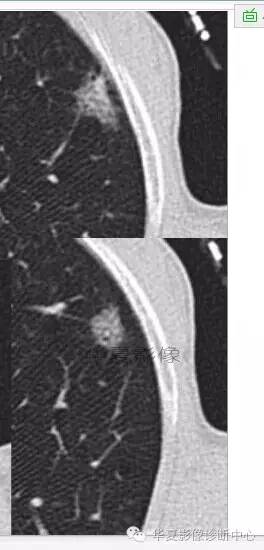

磨玻璃结节良恶性影像分析策略磨玻璃结节良恶性影像分析策略 这个按常规看到血管由凹陷处进去常规95%考虑癌,可是这里却不是

除非说这里GGO边缘稍模糊一些

宽基底与胸膜相连

近端有模糊的高密度影